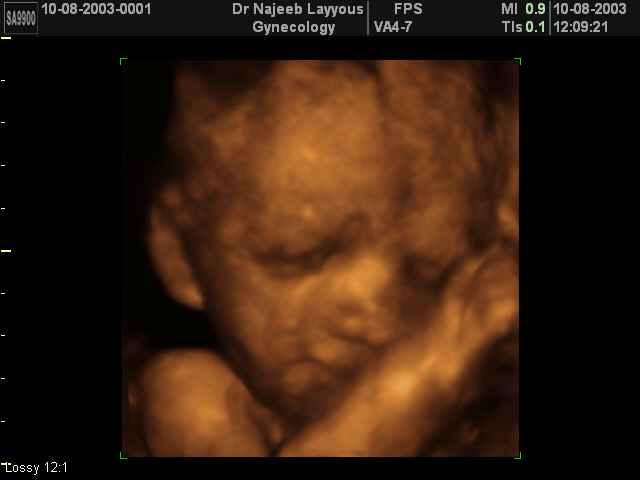

صور لوجه الجنين بجهاز الالتراساوند ثلاثي الأبعاد | الدكتور نجيب ليوس

صور لوجه الجنين بجهاز الموجات فوق صوتية ثلاثي الأبعاد